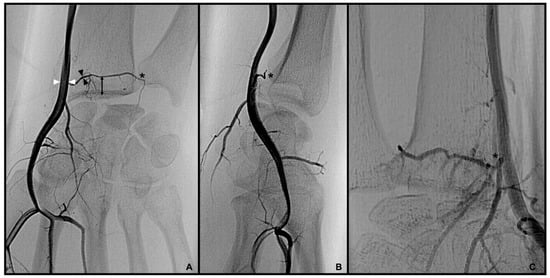

3.2. Dorsal Carpal Branch of the Ulnar Artery (DCBUA)

distance from the DCBUA to the styloid process of the ulnar (DCBUA = dorsal carpal branch of the ulnar artery).